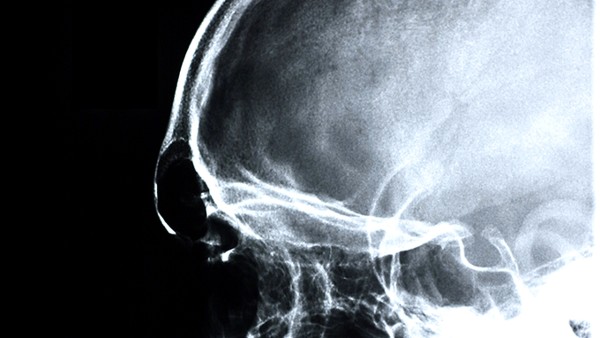

大家都晓得,药物,在很多疾病的治疗当中都起到了重要的作用,不仅可作为首选,有的时候,还是主要的方法,比如在癫痫的治疗上,但是,同时大家应该也知道,那就是药物治疗的话,也是有很多讲究的,有着不少的禁忌,所以为了避免大家用错药物,今天我们主要来介绍一下癫痫患者不宜使用的中药与西药。如果你有癫痫的情况,不妨来看一下吧。